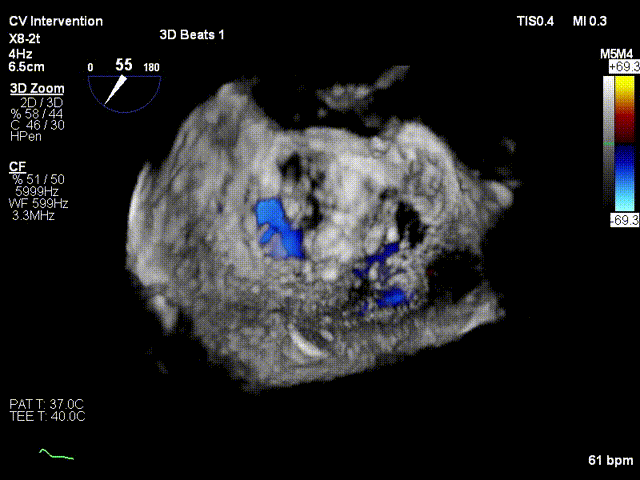

术前xPlane view提示:二尖瓣重度反流

术后xPlane view提示:二尖瓣反流显著减少

术前3D view提示:二尖瓣重度反流

术后3D view提示:二尖瓣反流显著减少